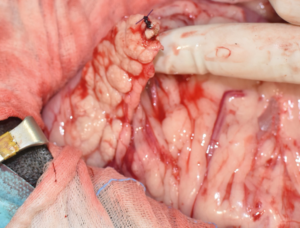

En casos de obstrucción biliar se debe considerar la duodenotomía y la colocación de un stent temporal en el colédoco, que sale al duodeno a través de la papila duonedal mayor, mientras se resuelve la compresión temporal por el absceso/inflamación (imágenes 2A y 2B). La colocación de stents de colédoco también se ha descrito en gatos.25-27 En esta especie, durante este procedimiento se debe tener cuidado de no cateterizar el conducto pancreático debido a la conexión anatómica entre el conducto pancreático y el conducto biliar común.28

Imágenes 3A – 3I. Secuencia de imágenes quirúrgicas en un perro (con las imágenes del TC), durante una pancreatectomía parcial del lóbulo izquierdo y cuerpo del páncreas, usando un sellador vascular/tisular, por carcinoma pancreático.